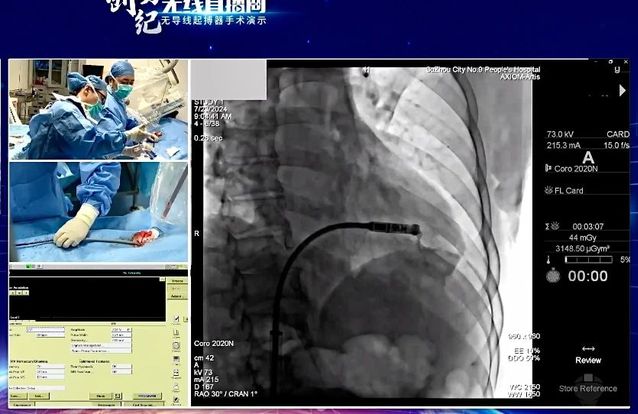

7月24日,“创势纪·无线直播间—苏皖区域无导线起搏器手术演示”在线上举行,金沙娱乐城app 心血管内科主任吴雁鸣参与手术演示,助力提升区域心血管病防治水平。本次活动由江苏省医学会心血管病学分会副主任委员、苏州市心血管病学分会主任委员、苏州大学附属第一医院心内科主任蒋廷波主持,汇聚了一大批专家教授开展手术演示和线上探讨,通过学术交流积极推动苏皖地区心血管病防治水平的进一步提高。

早在2021年,金沙娱乐城app 心血管内科就积极引入和开展无导线心脏起搏器植入术,是我区首家成功独立开展无导线起搏器植入手术的医院。心血管内科主任吴雁鸣是我区首位独立无导线起搏器术者,目前已成功独立植入近30例,受益人群大多为高龄老人,其中年龄最大的患者接受手术时已经103岁。

无导线起搏器,代表心脏起搏领域**技术。无导线起搏器(Micra),俗称胶囊起搏器,是目前世界上最小最轻的起搏器,直径6.7mm,长度25.9mm,重量仅1.75g,是国际前沿的先进起搏技术。虽然小,但其电池续航能力强,工作寿命长达12年,植入后还可以接受1.5T/3.0T核磁共振检查。患者无切口、无伤疤、无凸起、无束缚,几乎感觉不到它的存在,是看不见的起搏器,就像默默守护心律失常患者心脏健康的“隐性保镖”。

这一技术的成熟推广,对区域患者健康有着重要意义。植入心脏起搏器主要针对严重缓慢性心律失常的患者。传统的心脏永久起搏器由脉冲发生器和电极导线组成,医生通过腋静脉或锁骨下静脉将起搏器电极导线送至右心房或右心室,在患者胸前区胸大肌处制作与起搏器大小合适的囊袋,以容纳脉冲发生器。无导线起搏器不同于传统起搏器的地方在于:它不需要使用导线将脉冲发生器连接到起搏电极上。相反,它将脉冲发生器和起搏电极集成在一起,以微缩胶囊的形式直接植入患者的心腔内部。